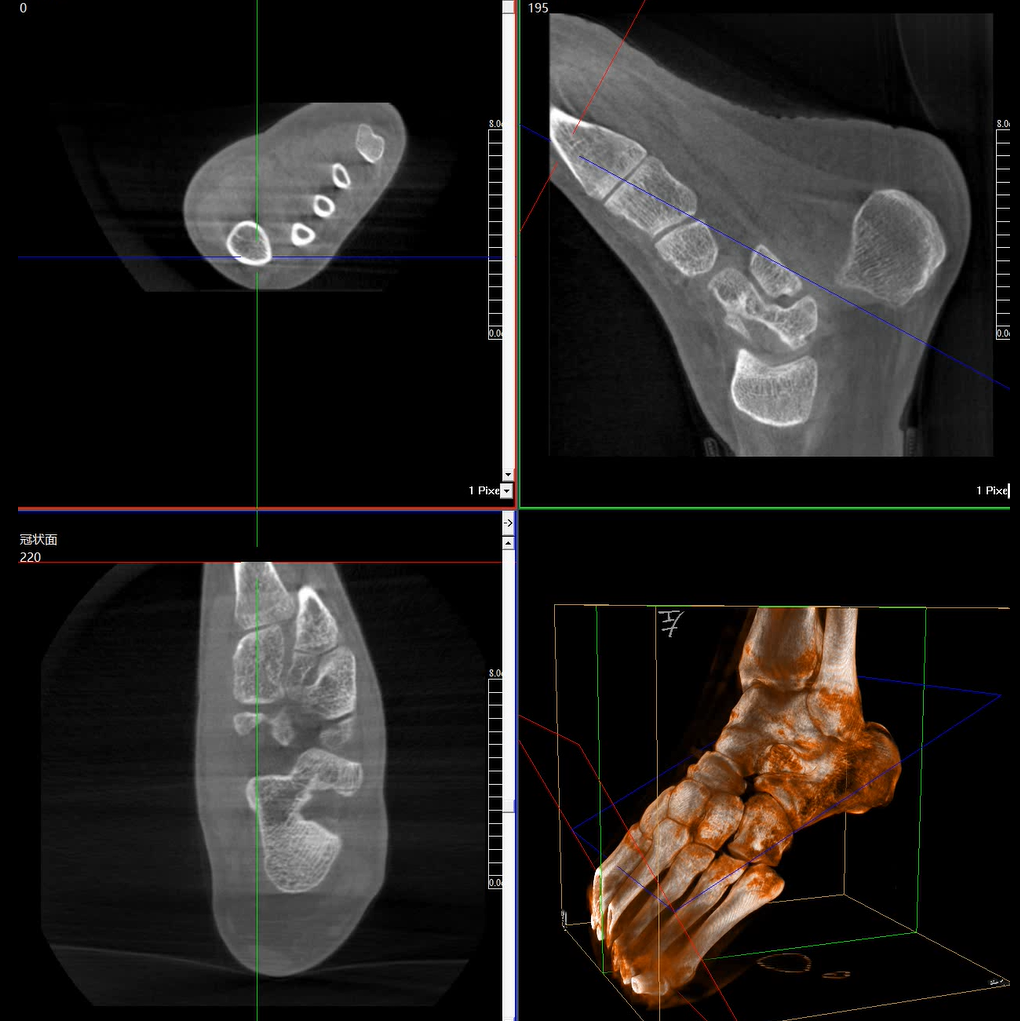

術(shù)中三維成像和橫斷面圖像提供多角度的手術(shù)診斷信息,輔助醫(yī)生進行術(shù)中評估判斷,諸如骨折復(fù)位情況和內(nèi)植入螺釘?shù)某叽绾臀恢?,輔助手術(shù)更好地完成。

提供更大的術(shù)中三維成像視野,采集更多圖像信息,可一次拍全全段頸椎、全段腰椎、七節(jié)胸椎、雙側(cè)骶髂關(guān)節(jié)、股骨頭及單側(cè)盆骨。